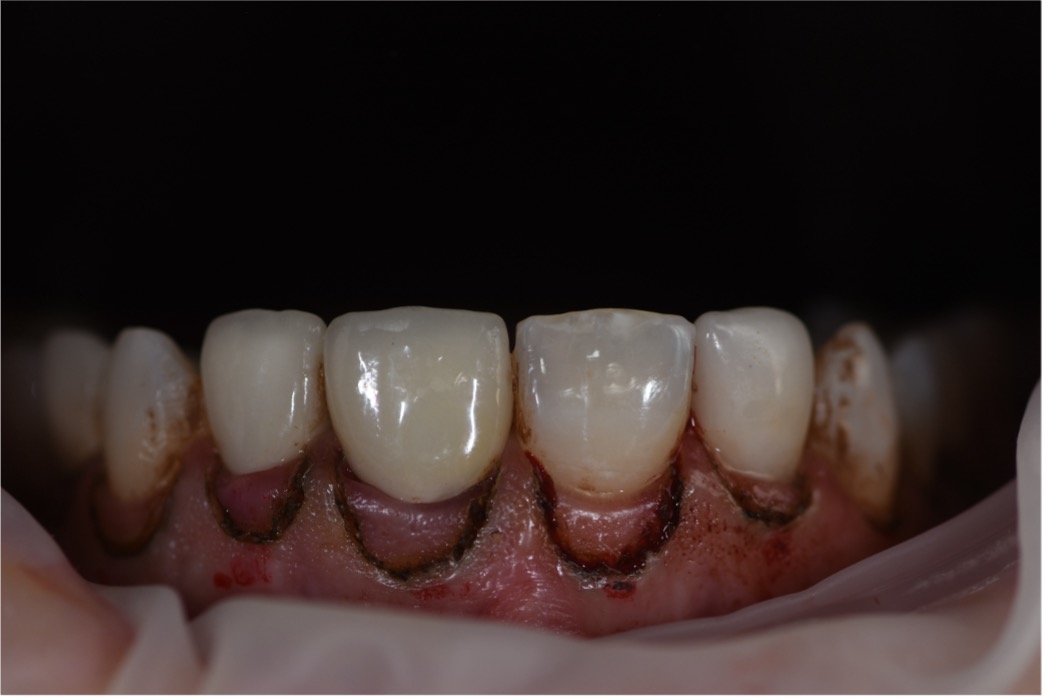

architecture. These restorations were fabricated with high precision, ensuring excellent fit, esthetics, and durability. The bonding procedure was carried out with attention to Figure 19: 3D Printed Surgical Guide Try In Figure 20: Close Up Difference between 3D Printed Mockup and Initial Teeth Figure 21: During digital crown lengthening Figure 22: Post Op Intraoral Picture detail, followed by polishing to achieve a natural and vibrant finish. The completed smile

was assessed for functionality, esthetics, and the patient’s satisfaction.